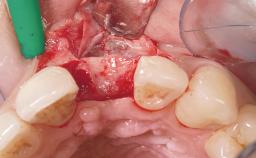

Immediate Placement of an Implant in a Maxillary Right Central Incisor Site

A 30-year-old female patient was referred to the office for the treatment of tooth 11. Her chief concern at the initial visit was to inquire, “Why is my tooth pink?” Upon clinical examination, it was determined that tooth 11 had a previous history of trauma and that the clinical crown had become noticeably pink in color as a result of internal resorption. This diagnosis was confirmed radiographically, indicating a large radiolucency involving the central and distal portions of the clinical crown. It was determined that restoration of this tooth was not possible, and that extraction was indicated. The presence of a mid-line diastema, which the patient wanted to reproduce, directed the treatment plan for tooth replacement utilizing a dental implant.